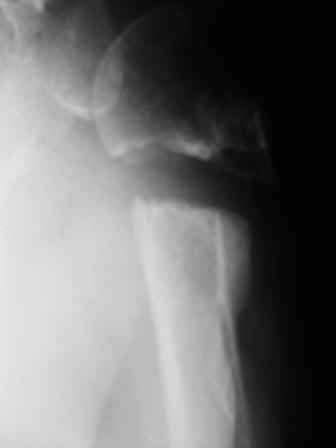

Уважаемые коллеги! Госпитализирована больная 51года. Травма - перелом хирургической шейки плеча в феврале 2009г.

Лечилась по месту жительства Лонгетной гипсовой повязкой. На фоне сформировавшегося ложного сустава работает маляром. Объем движений и сила естественно ограничены. При обсуждении тактики лечения возникли разногласия по поводу вида остеосинтеза и егоцелесообразности.